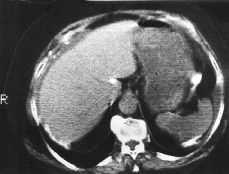

La radiografía simple de abdomen muestra múltiples áreas calcificadas distribuidas difusamente (Fig. 1). Se realiza TC abdominal donde se define una masa pélvica, heterogénea, parcialmente calcificada, con bordes mal definidos, sugestiva de neoplasia ginecológica. También se observa engrosamiento mesentérico y de épiplon mayor, parcialmente calcificado (Fig. 2), calcificaciones perihepáticas, periesplénicas y ascitis, (Fig. 3). Hallazgos sugestivos de carcinomatosis peritoneal abundantemente calcificada.

Figura 3. Calcificaciones perihepáticas y periesplénicas.